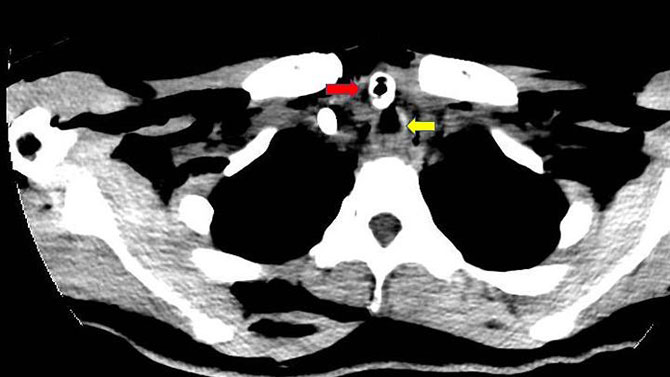

术前CT片红箭头为气管插管;黄箭头为断裂气管下段(位于插管后方)